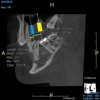

(4.) In a CBCT image axial view, the MB1 and MB2 canals are readily visible in tooth No. 14, and in the coronal view, these two separate canals can be seen to merge into a single apical opening.

Figure 4

Being able to see the number and shape of the canals accurately prior to treatment is the desire of any clinician who performs endodontics. Research suggests that, due to improved diagnostic accuracy, the final treatment plan may change in up to 50% of endodontic cases if CBCT is used rather than traditional 2D imaging.14,15 The question of whether or not a patient has an MB2 canal can be answered prior to opening the access preparation (Figure 4 and Figure 5). Visualizing single canals that bifurcate in the apical or middle third of the root or those that merge to a single apical opening can help clinicians to understand their instrumentation needs in advance. In addition, the ability to measure the length and shape of a canal planned for instrumentation prior to utilizing an apex locator helps to confirm any measurements obtained by other means. It should also be noted that the ability to see a pathosis in 3 dimensions and to involve the patient in understanding his or her condition prior to any decision-making allows for definitive treatment planning. In fact, many patients have pathoses associated with teeth that are asymptomatic that remain unknown to them until they are visually presented with the evidence (Figure 6).